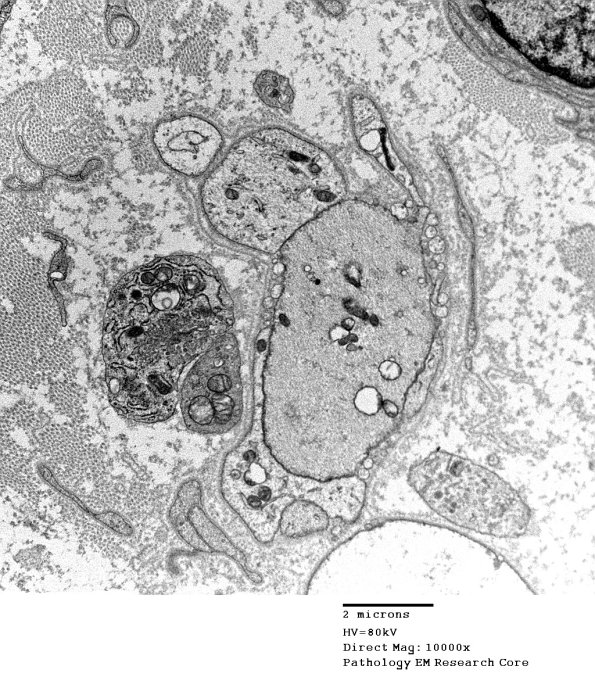

The completion of the demyelinating process results in naked axons which may be difficult to separate from adjacent Schwann cell processes at low magnifications. (electron micrographs)